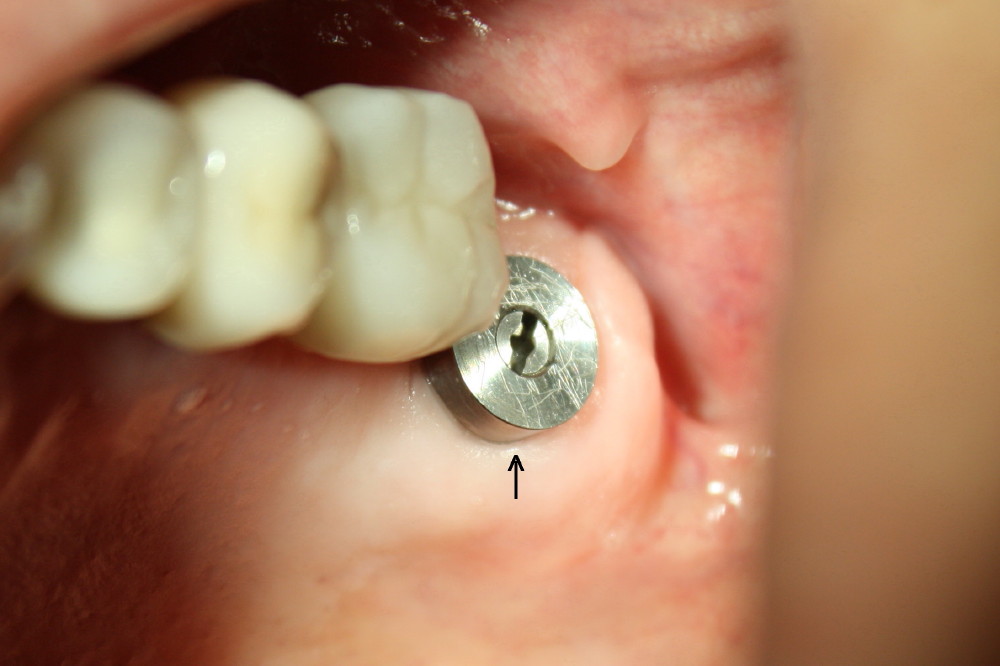

图一显示即刻植牙(箭头)术后接近三个月,明显偏向鄂侧。术后四个月,装上台基(图二:A),在种植体和台基上面制备牙冠,戴上牙冠(图三:C),咬合面挺正常。颊侧远中观(图四)显示这个牙冠有悬臂桥味道,但是这个上颌第二磨牙功能尖在鄂侧(P; B:颊侧),使用Zirconia材料做牙冠,估计不会出现陶瓷断裂问题。直径大的种植体和台基共同支撑牙冠(图二),所以后者也不容易脱落。